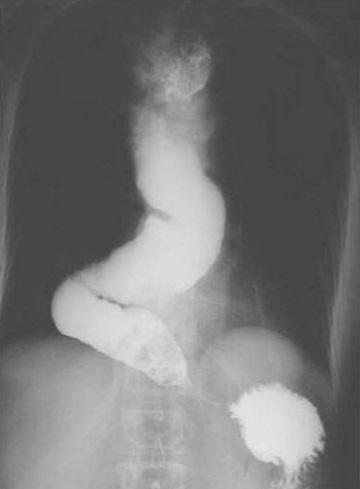

[Congenital alacrima revealing a Allgrove syndrome: report of three cases].